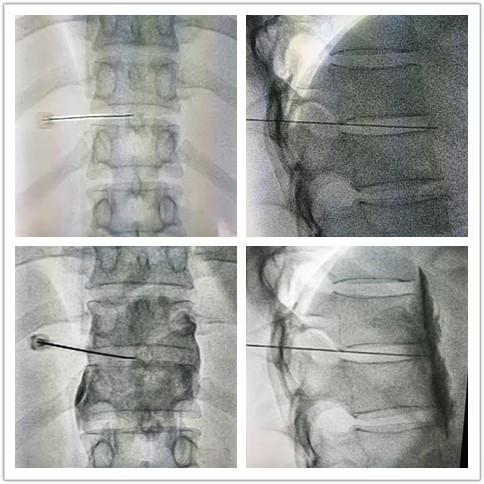

近日,我院疼痛门诊成功为一位胰腺癌腹部顽固性重度疼痛患者进行经皮穿刺内脏大小神经毁损术。该患者女性,44岁,上腹部顽固性重度疼痛6月,在我院确诊胰腺癌。服用阿片类镇痛药及使用静脉镇痛泵疼痛缓解不明显,NRS评分10分。手术是在DSA引导下,经后背部第11-12胸椎间盘间隙将一根细穿刺针经皮肤刺入,针尖穿过间盘后就到达内脏大小神经分布区,先注入局麻药进行神经阻滞术,待患者腹部有温热感,疼痛消失,然后注入无水乙醇进行神经毁损治疗。整个手术过程持续30分钟,术后患者上腹部疼痛完全缓解,无手术并发症发生,生活质量得到了显著提高。